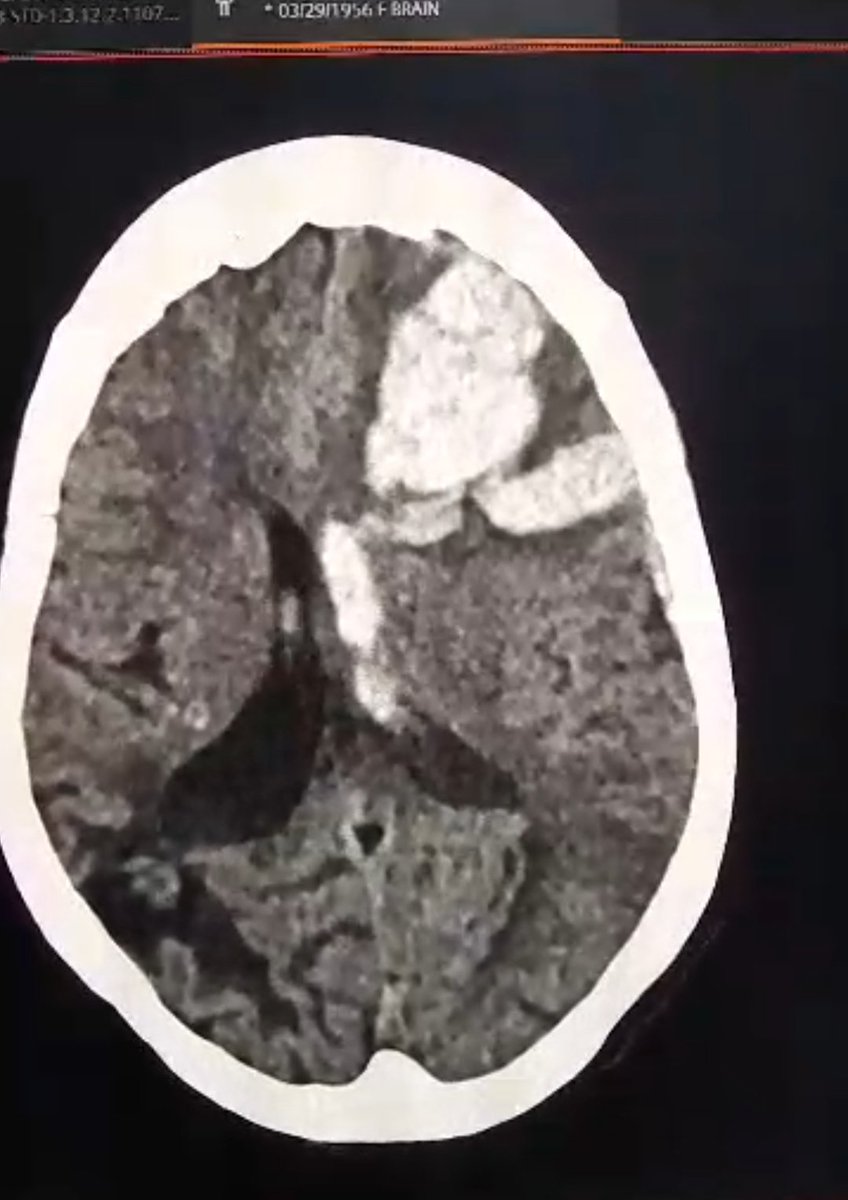

76 yo sudanese women from Darfur needing urgent care and surgery for excessive brain hemorrhage

Initial amount to be raised:

£1800

For Neuro-critical care, medications and surgical fees